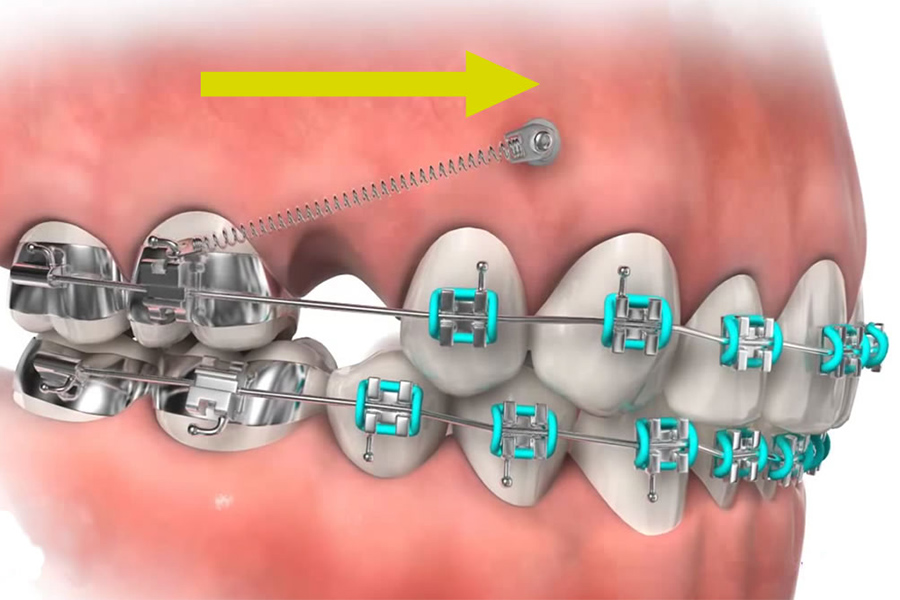

インプラントアンカー(ミニスクリュー)

矯正治療では、歯を動かす際に支えとなる「固定源」を作らなくてはならない場合があります。特に、根が太く動かしにくい奥歯を前後に大きく移動する場合や、歯を歯ぐきの方向に押し込む移動(圧下)を行う際は非常に重要になってきます。

この問題を解消するため、歯以外の部分(歯ぐき)にミニインプラントを埋め込み、そこを固定源としてワイヤーをつなげて歯並びを整える方法をTemporary Anchorage Device:TADと呼びます。

この方法を応用すると、効率よく歯が動いて治療期間を短縮できたり、矯正のための抜歯を回避できることもあります。